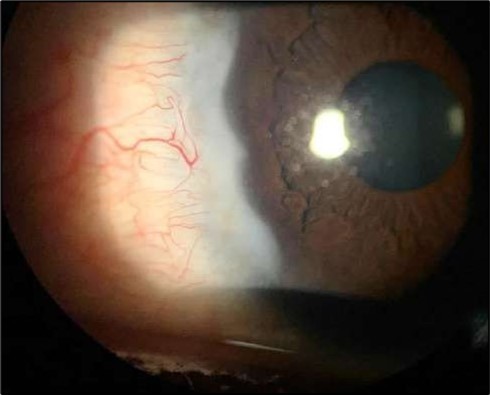

On the current presentation, Snellen VA was 6/6 in the right eye and 6/9 in the left eye, with normal IOP. The left eye demonstrated mild upper lid edema and intense nasal ciliary injection. Slit-lamp evaluation revealed a crescentic area of stromal corneal melting between 7 and 10 o’clock nasally, with overhanging edges and a fluorescein-positive base. No corneal infiltrates were present, and the surrounding stroma remained clear. The anterior chamber was deep and quiet, lens was transparent, pupil was round and reactive & normal posterior segment. Anterior segment optical coherence tomography (AS-OCT) confirmed a localized ulcer, measuring 1324 µm in horizontal width and extending to a depth of 380 μm, compared with an adjacent healthy corneal thickness of 824 µm, corresponding to approximately 46.1% stromal thinning (Figure 1a, Figure 1b, Figure 1c)

Figure 1a.Left eye (OS), on presentation. Slit-lamp image: crescent-shaped peripheral corneal ulceration located nasally, with severe adjacent conjunctival injection, peripheral thinning, and stromal infiltration.

Despite systemic and topical management over one month, the epithelial defect persisted, indicating refractoriness to medical therapy. OCT imaging showed ulcer depth reduction to nearly 42% stromal thinning and width of 1180 µm, highlighting partial corneal healing. In view of the persistent ulcer and ongoing local inflammation, a conjunctival resection was performed to excise the perilimbal inflammatory focus and promote corneal repair Figure 3a and 3b.

Serial anterior segment OCT was employed throughout treatment to monitor corneal changes and response to interventions. Figure 7a, Figure 7b, Figure 7c, Figure 7d illustrate the ulcer’s progression: initial severity, minimal early response to medical therapy, post-operative healing after conjunctival resection, and sustained recovery at six-month follow-up.

Figure 7a.(At presentation): AS-OCT reveals a crescent-shaped peripheral corneal ulcer with marked stromal thinning of 380 µm in depth and complete loss of the overlying epithelium. The ulcer spans 1324 µm in width. The ulcer base appears concave with hyperreflective stromal margins, and a distinct overhanging edge is visible at the inner margin.

Figure 7b.(Following systemic immunosuppression): AS-OCT shows a reduction in ulcer depth to 338 µm and a narrower ulcer width of 1180 µm, suggesting minimal therapeutic response. The ulcer bed remains irregular with persistent stromal hyperreflectivity, likely due to ongoing inflammation. The overhanging edge is less prominent, and partial re-epithelialization is observed.